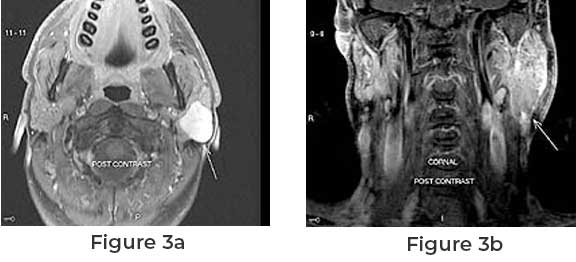

Parotid tumors are typically diagnosed through a combination of clinical examination, imaging tests such as MRI or CT scans, and biopsy. Fine needle aspiration (FNA) biopsy is often used to determine whether the tumor is benign or malignant by extracting a small sample of cells from the tumor for analysis.